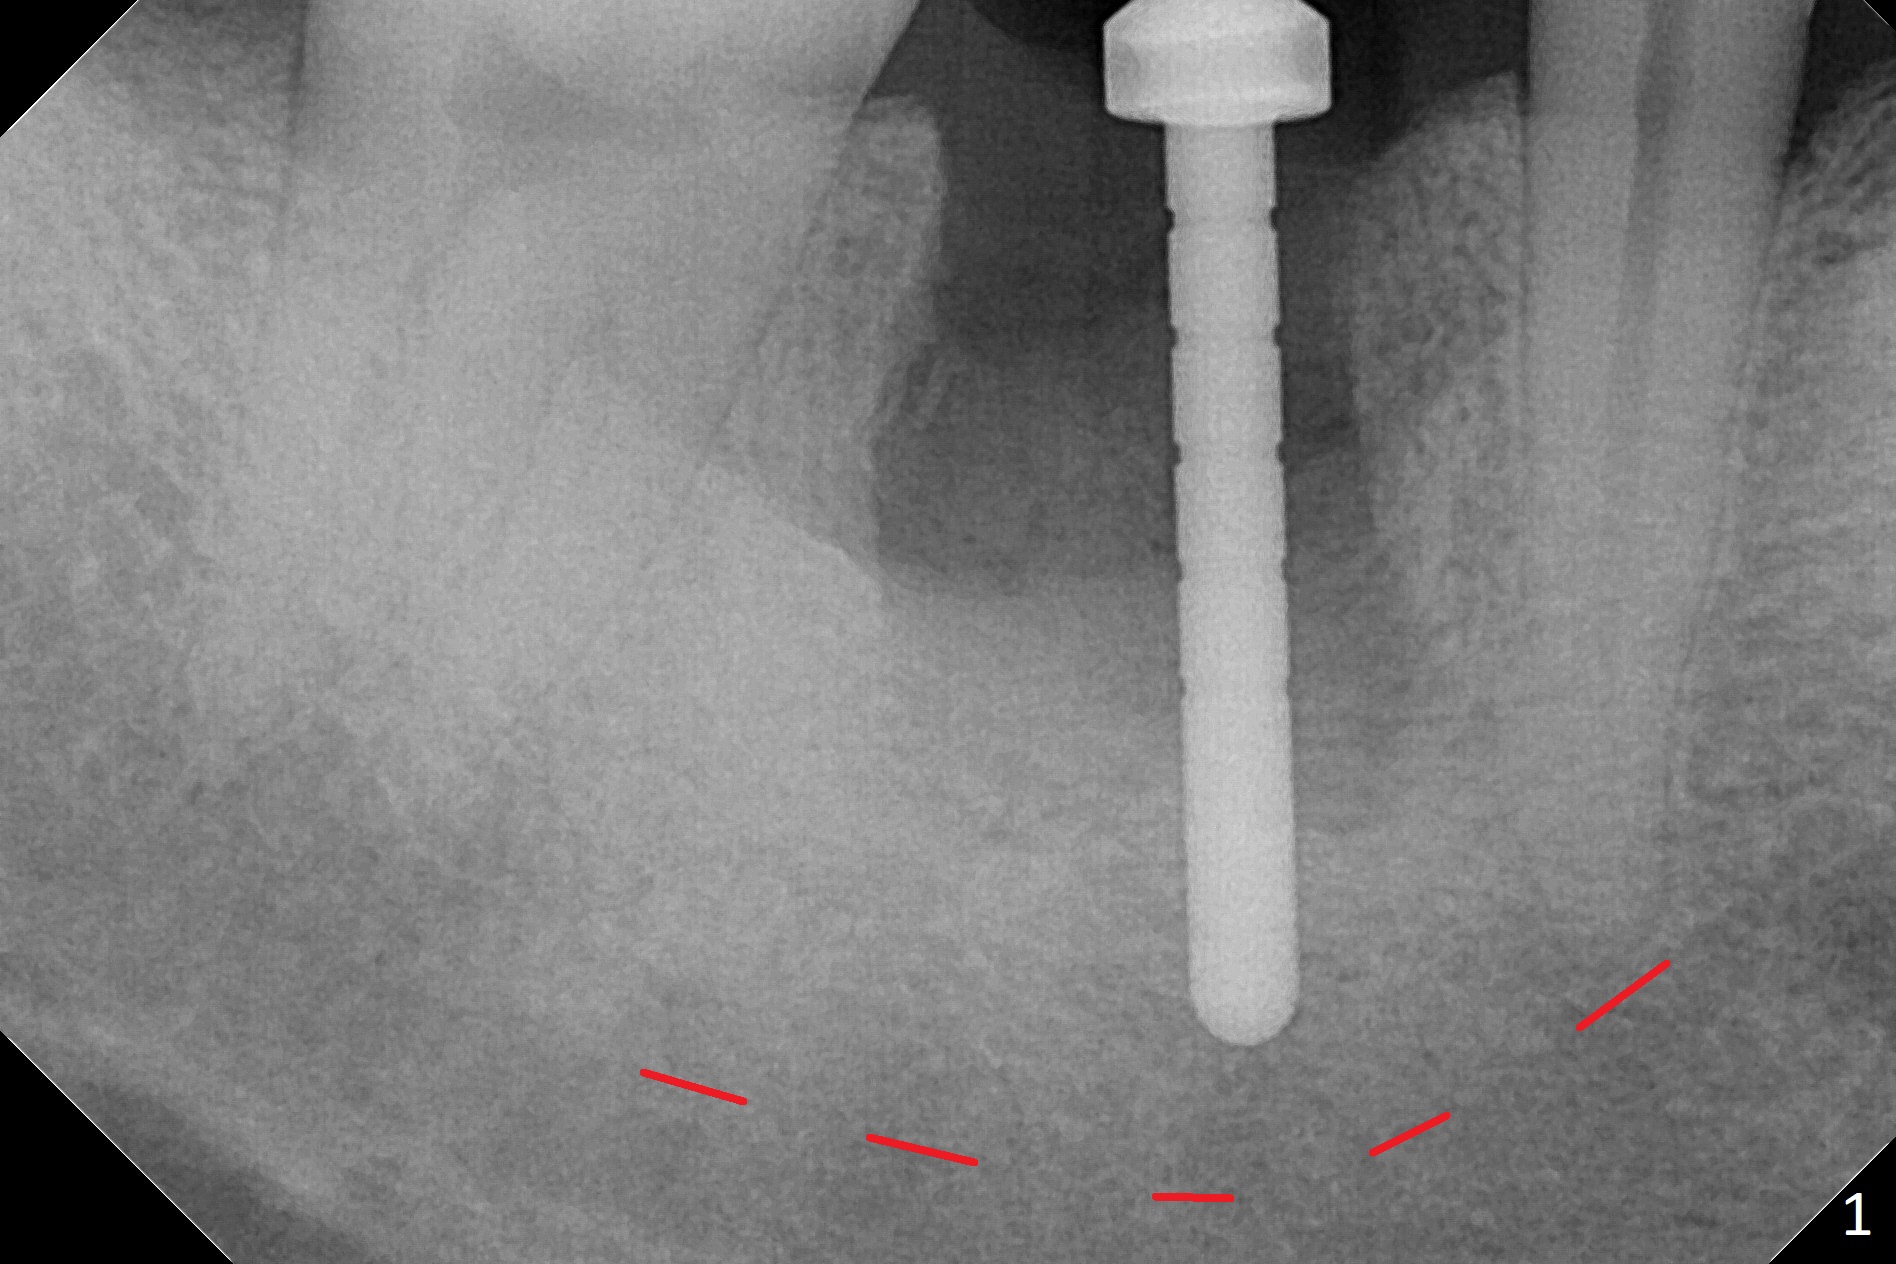

After the tooth #30 is extracted, the socket is 18 mm deep and the lingual plate is 4 mm tall. With hemorrhage, visibility of the socket, especially the bottom, is poor. The septum is almost completely defective. Following removal of the most buccal portion of the septum, osteotomy is initiated as buccal as possible, but it is mesial (Fig.1). In spite of effort to move the osteotomy distal, the osteotomy remains mesial and superficial (Fig.2 with 5 mm tap drill). Pain control is poor with infiltration. It appears that the smaller osteotomy (Fig.2 yellow line) may have extended close to the superior border of the Inferior Alveolar Canal (red line). It appears that there is 8.5 mm bone distal with ~ 2 mm clearance. After mandibular block, a new osteotomy is made distal; when a 3.8 mm drill is being used, there is hemorrhage from the osteotomy with apparent violation of the Canal integrity (Fig.3,4). But hemostasis is achieved with gauze pressure. A 5x13 mm implant is placed superficially (Fig.5) with a trace of the previous osteotomy (yellow line) and deep space created by the mesial osteotomy (*). Apparently the pathological and iatrogenic defects are filled with allograft (Fig.6 *). Guided surgery could have avoided the mesial osteotomy.